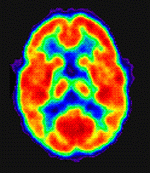

oggi l'antimateria

è usata ogni giorno in medicina per analizzare lo stato del cervello, tramite

la tecnica chiamata Positron Emission Tomography (PET). La PET è un metodo di

indagine che permette di misurare funzioni metaboliche e reazioni biochimiche

in vivo ed ha larga applicazione nelle neuroscienze, in oncologia e in

cardiologia. Essa utilizza positroni che si annichilano scontrandosi con gli

elettroni. I positroni sono emessi da una sostanza radioattiva, un isotopo,

combinato con una molecola metabolica, per esempio il glucosio, iniettata nel

sangue. I positroni emessi dall'isotopo si annichilano quasi immediatamente

incontrando gli elettroni ed emettono due raggi γ in direzioni opposte.

Questi raggi provenienti dal corpo del paziente permettono ad un computer di

costruire una mappa della regione celebrale dalla quale provengono; la loro

emissione è più intensa nella regione in cui è alta la concentrazione di

positroni ovvero dove vi è maggior quantità di sangue. Il computer

contraddistingue le diverse regioni con appostiti colori: rosso per le aree di

attività più intensa, arancione e giallo per quelle mediamente coinvolte e blu

per quelle non interessate. L'immagine permette quindi di controllare l'organo

e di rilevare eventuali anomalie. È una tecnica invasiva tuttavia non

pericolosa in quanto la quantità di radiazioni assorbita dal paziente è minima.

La PET ha molte applicazioni ed è il test più sicuro per l'identificazione del

morbo di Alzheimer nelle fasi iniziali ed è l'unico strumento per fotografare il

funzionamento di particolari aree del cervello collegate alle emozioni.

Tomografia a emissione di positroni

Nella foto, la PET eseguita sul cervello di un individuo evidenzia l'attività delle cellule cerebrali a riposo e durante tre tipi di stimolazione auditiva.